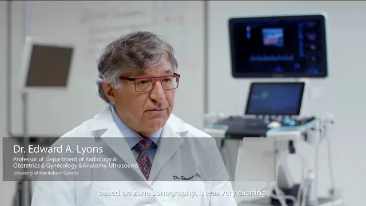

Seit der Gr├╝ndung des Unternehmens hat Mindray fortlaufend neue Wege zur Verbesserung der diagnostischen Zuverl?ssigkeit erforscht. Angetrieben von der revolution?rsten Technologie ZONE Sonography?, bringt die neue ZST+ Plattform von Resona 7 die Ultraschallbildqualit?t durch Zonenerfassung und Kanaldatenverarbeitung auf ein h?heres Niveau.

Neben der erstklassigen Bildqualit?t verbessert Resona 7 auch die klinischen Forschungsm?glichkeiten mit dem revolution?ren V Flow f├╝r die vaskul?re h?modynamische Bewertung und der intelligentesten Ebenenerfassung aus 3D-Datens?tzen f├╝r die f?tale ZNS-Diagnose. Mit der Kombination aus intuitiver, gestenbasierter Multi-Touch-Bedienung und allen wichtigen klinischen Funktionen ist das Resona 7 ein echter Wegbereiter f├╝r neue Ultraschall-Innovationen.

Die St?rken des Resona 7 sind bis ins kleinste Detail durchdacht. Seine erstklassige Bildqualit?t ist das Ergebnis einer erfolgreichen Fusion. Mindray und Zonare Medical Systems haben ihren Kernkompetenzen geb├╝ndelt, um ein Premiumsystem Wirklichkeit werden zu lassen. Dank der Vector Flow-Funktion k?nnen bei Gef??untersuchungen mehr als 400 Bilder pro Sekunde dargestellt werden. Somit entstehen ganz neue M?glichkeiten der Diagnose.